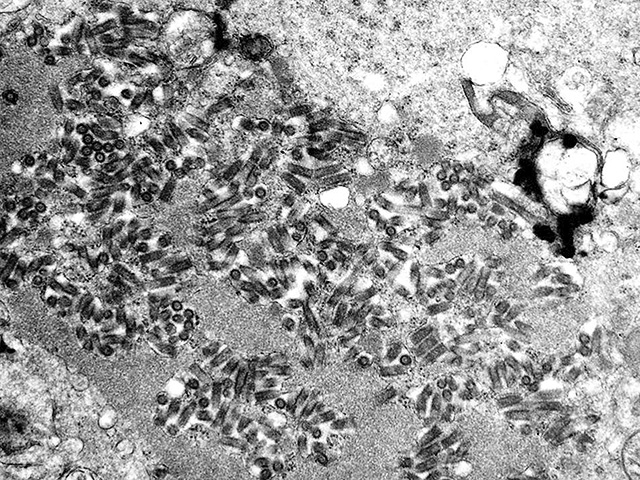

Модель искусственного интеллекта может точно прогнозировать активность генов в каждой клетке человека, что дает возможность получить данные о клеточных функциях и механизмах заболеваний.

Международная группа исследователей разработала модель ИИ, обученную на данных более 1,3 миллиона клеток, которая способна с большой точностью предсказывать экспрессию генов в редких типах клеток. Система уже выявила механизмы, связанные с детской лейкемией, и может помочь в исследовании "темной материи" генома, где происходят большинство мутаций, связанных с раком. Разработка может значительно преобразовать подход исследователей к изучению различных областей, от онкологии до генетических заболеваний.